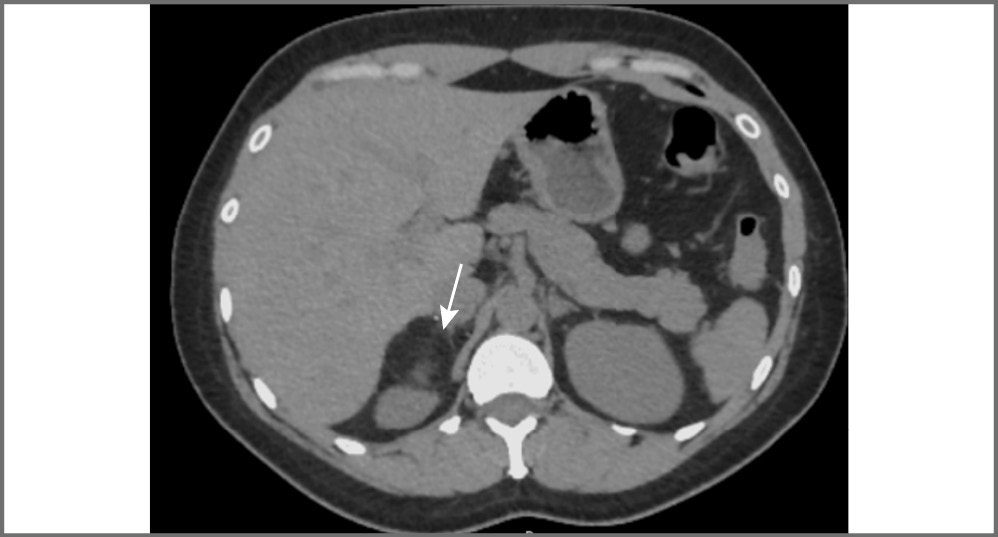

Адренокортикальный рак является наиболее частой первичной злокачественной опухолью, исходящей из коркового слоя надпочечника, и составляет менее 5% всех инциденталом [1]. Как правило, АКР представляет собой крупное образование (от 2 до 40 см, в среднем 11–12 см) с неровными нечеткими контурами, повышенной плотности (более 10 ед. Н). При болюсном контрастном усилении образование умеренно неоднородно накапливает контрастный препарат со слабым его вымыванием в отсроченную фазу. Для данного образования характеры зоны некроза и кровоизлияний, а также кальцинаты, которые встречаются в 30% случаев [16]. При контрастировании возможно обнаружение тонкого капсулоподобного ободка контрастирования (рис. 4) [17]. Необходимо учитывать, что АКР также может быть выявлен в структуре таких доброкачественных образований, как аденомы (в структуре коллизионной опухоли); рис. 5.

Рис. 4. Рак правого надпочечника. МСКТ, аксиальная проекция: а – нативная фаза; b – артериальная фаза; c – венозная фаза; d – отсроченная фаза. В теле правого надпочечника определяется округлой формы образование (стрелка) с четкими ровными контурами, неоднородной структуры, неравномерно накапливающее контрастный препарат.

Рис. 5. Коллизионная опухоль левого надпочечника (рак в структуре аденомы). МСКТ, аксиальная проекция: а – нативная фаза; b – артериальная фаза; c – венозная фаза; d – отсроченная фаза. В левом надпочечнике определяется округлое образование (стрелка) пониженной плотности с четкими ровными контурами, неоднородной структуры за счет наличия мягкотканых включений, интенсивно накапливающих контрастный препарат, со слабым его вымыванием в венозную и отсроченную фазы.

Для АКР характерны признаки злокачественности: инвазивный рост с вовлечением окружающих структур и органов или метастазы. Вовлечение почечной вены (9–19% наблюдений) чаще встречается при опухоли правого надпочечника и проявляется распространением опухоли в просвете данной вены, далее в нижней полой вене до правого предсердия [16, 18].